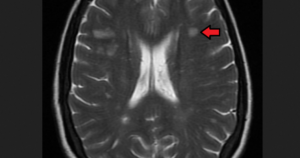

- Усиление сигнала от очагов после введения красящего вещества.

- Множественные очаги, которые накапливают контраст.

Применение контраста

Для усиления структур мозга с отсутствующим или поврежденным гематоэнцефалическим барьером применяют контрастирование. С этой целью используют водорастворимые парамагнитные вещества на основе гадолиния, они проявляют эффект с первой до пятнадцатой минуты после внутривенного введения.

Способность накапливать контраст связана с активностью воспалительного процесса в нервном волокне, он проникает в зону воспаления и отека, вызывает усиление сигнала на Т1-ВИ в виде кольца вокруг появившихся новых или растущих участков склероза.

Чем выраженней поражение нервного волокна – тем ярче изображение. Этот процесс происходит в старых очагах, патологических участках, локализующихся в коре и подкорковом сером веществе, где они обычно не видны на стандартных Т2-изображениях.

Применение Магневиста (парамагнитное контрастное вещество на основе гадолиниума) повышает процент выявляемых бляшек, что позволяет определять тяжесть заболевания, назначать адекватную терапию. Рассеянный склероз на МРТ выявляют в десять раз чаще по сравнению с клиническими проявлениями заболевания.